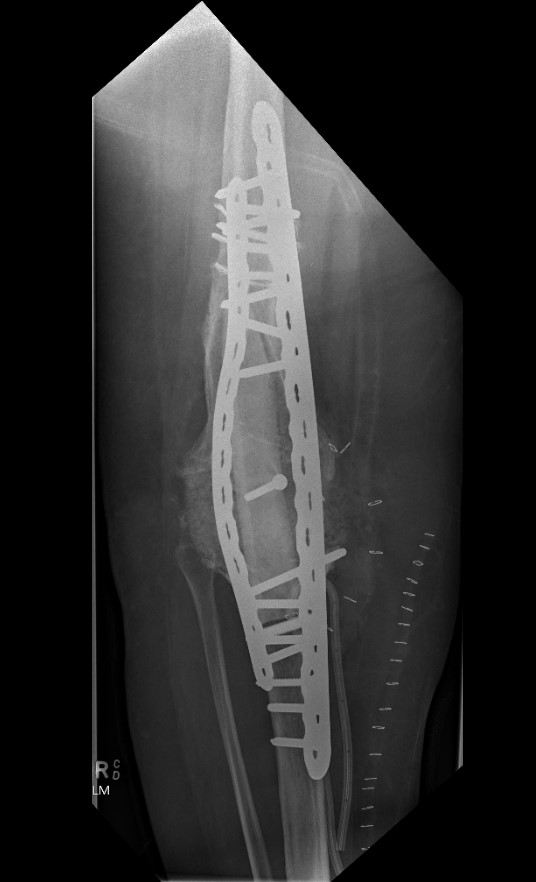

Dual plates

External Fixation